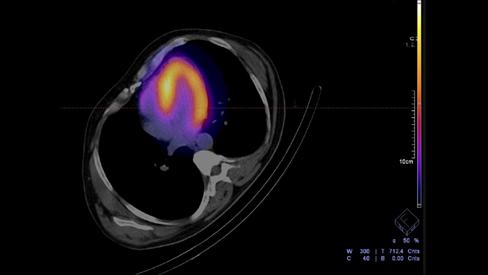

Rycina 4. Ocena techniką SPECT/CT (badanie po korekcji pochłaniania) – widoczne zaawansowane lewokomorowe zmiany chorobowe oraz objęcie przez proces chorobowy wolnej ściany prawej komory

Materiał Zakładu Medycyny Nuklearnej Krakowskiego Szpitala

Specjalistycznego im. św. Jana Pawła II.